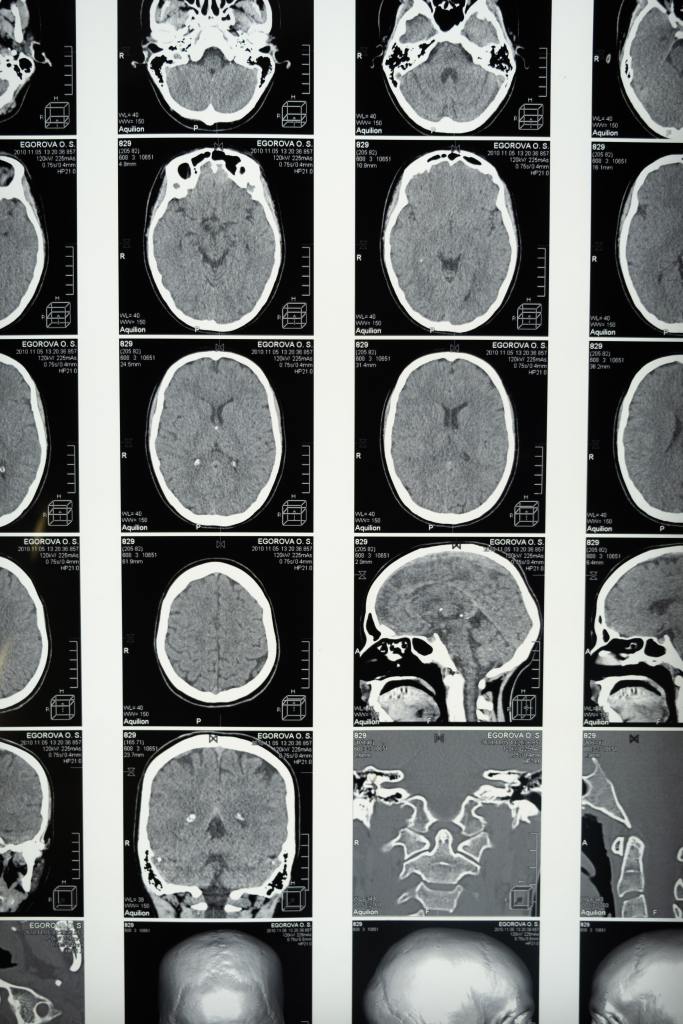

Ketamine works on your brain’s glutamate receptors. It regrows and reactivates parts of your brain called synapses that haven’t been working. It helps the brain’s ability to change, which can help it shift out of depression, helping with neuroplasticity. After the brain is “rewired” antidepressants and psychotherapy that didn’t work before ketamine treatments may help afterward.